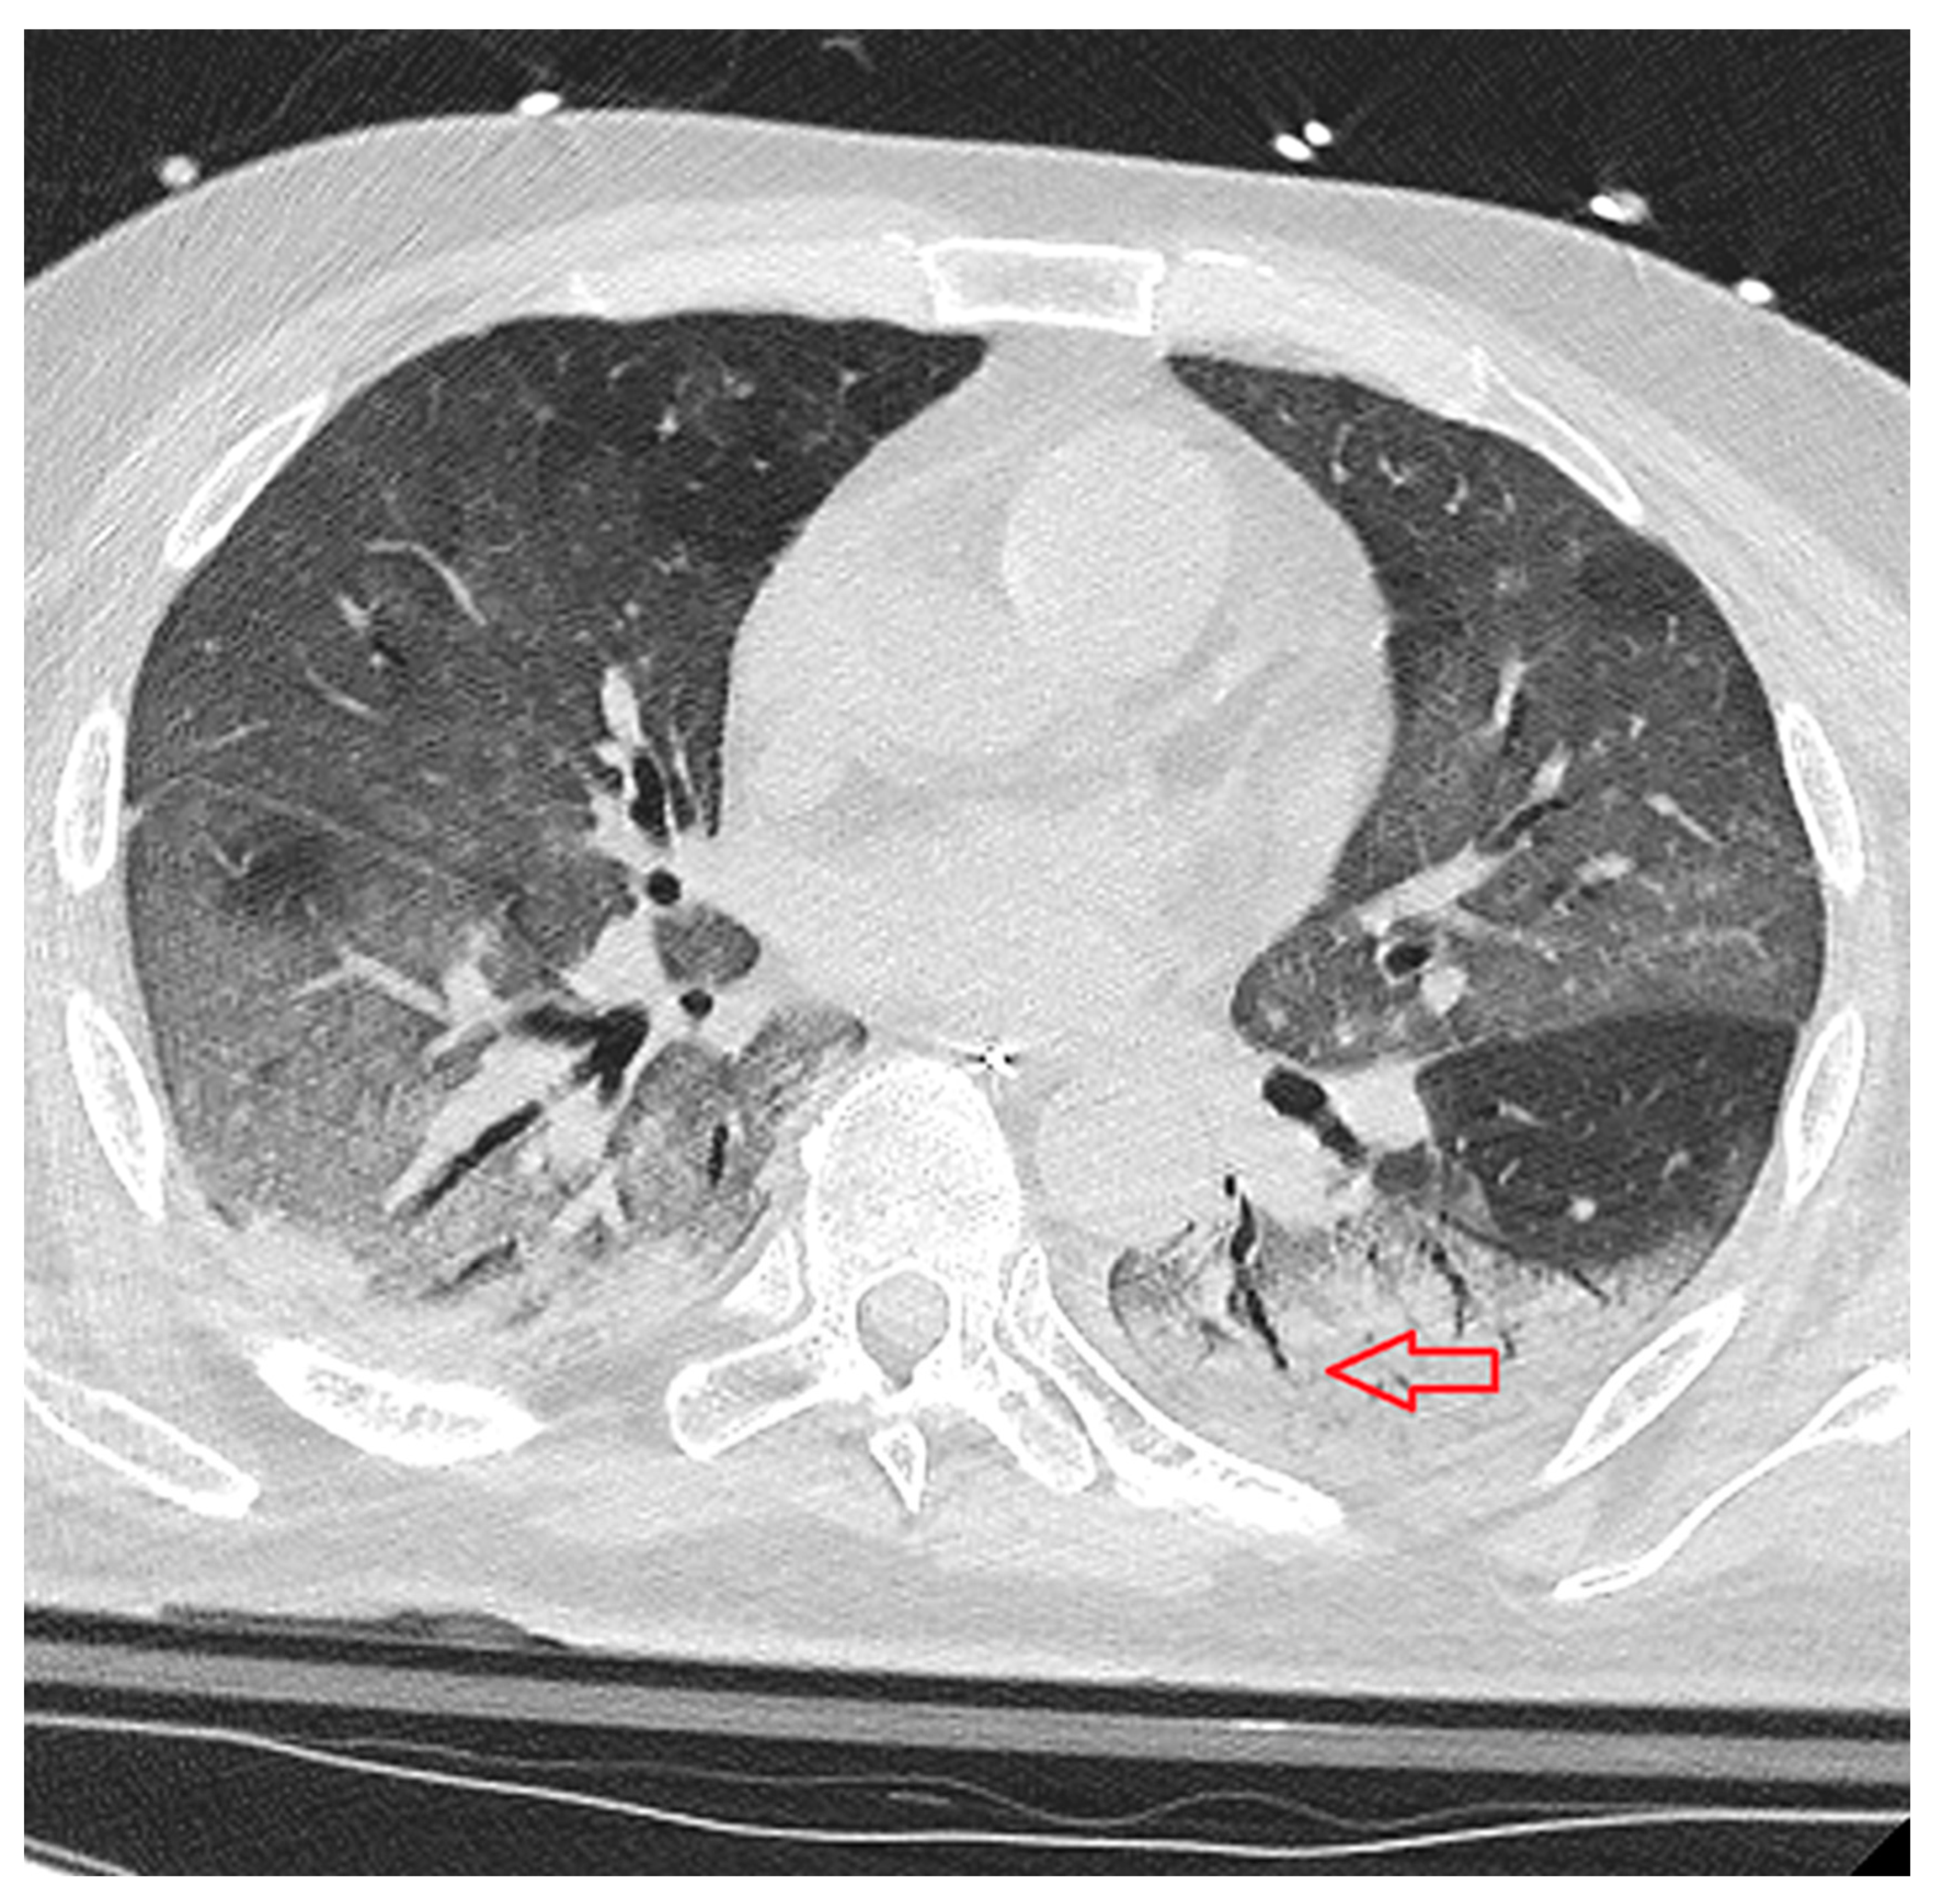

- Consolidation: homogeneous increase in lung parenchymal opacity obscuring the vascular margins and airway walls with an air bronchogram (pattern of air-filled bronchi on a background of opaque airless lung) (Figure 3);